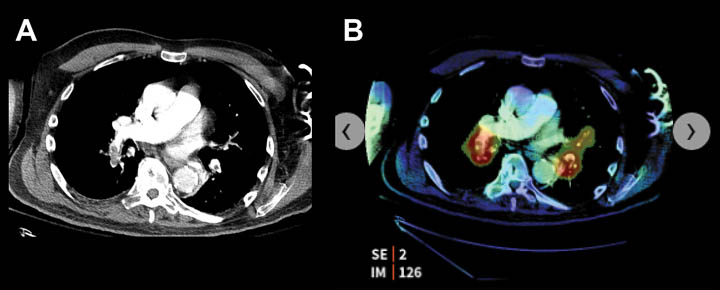

- CT angiogram of the chest with bilateral pulmonary emboli.

- AI based software highlights the emboli, color coded in red.